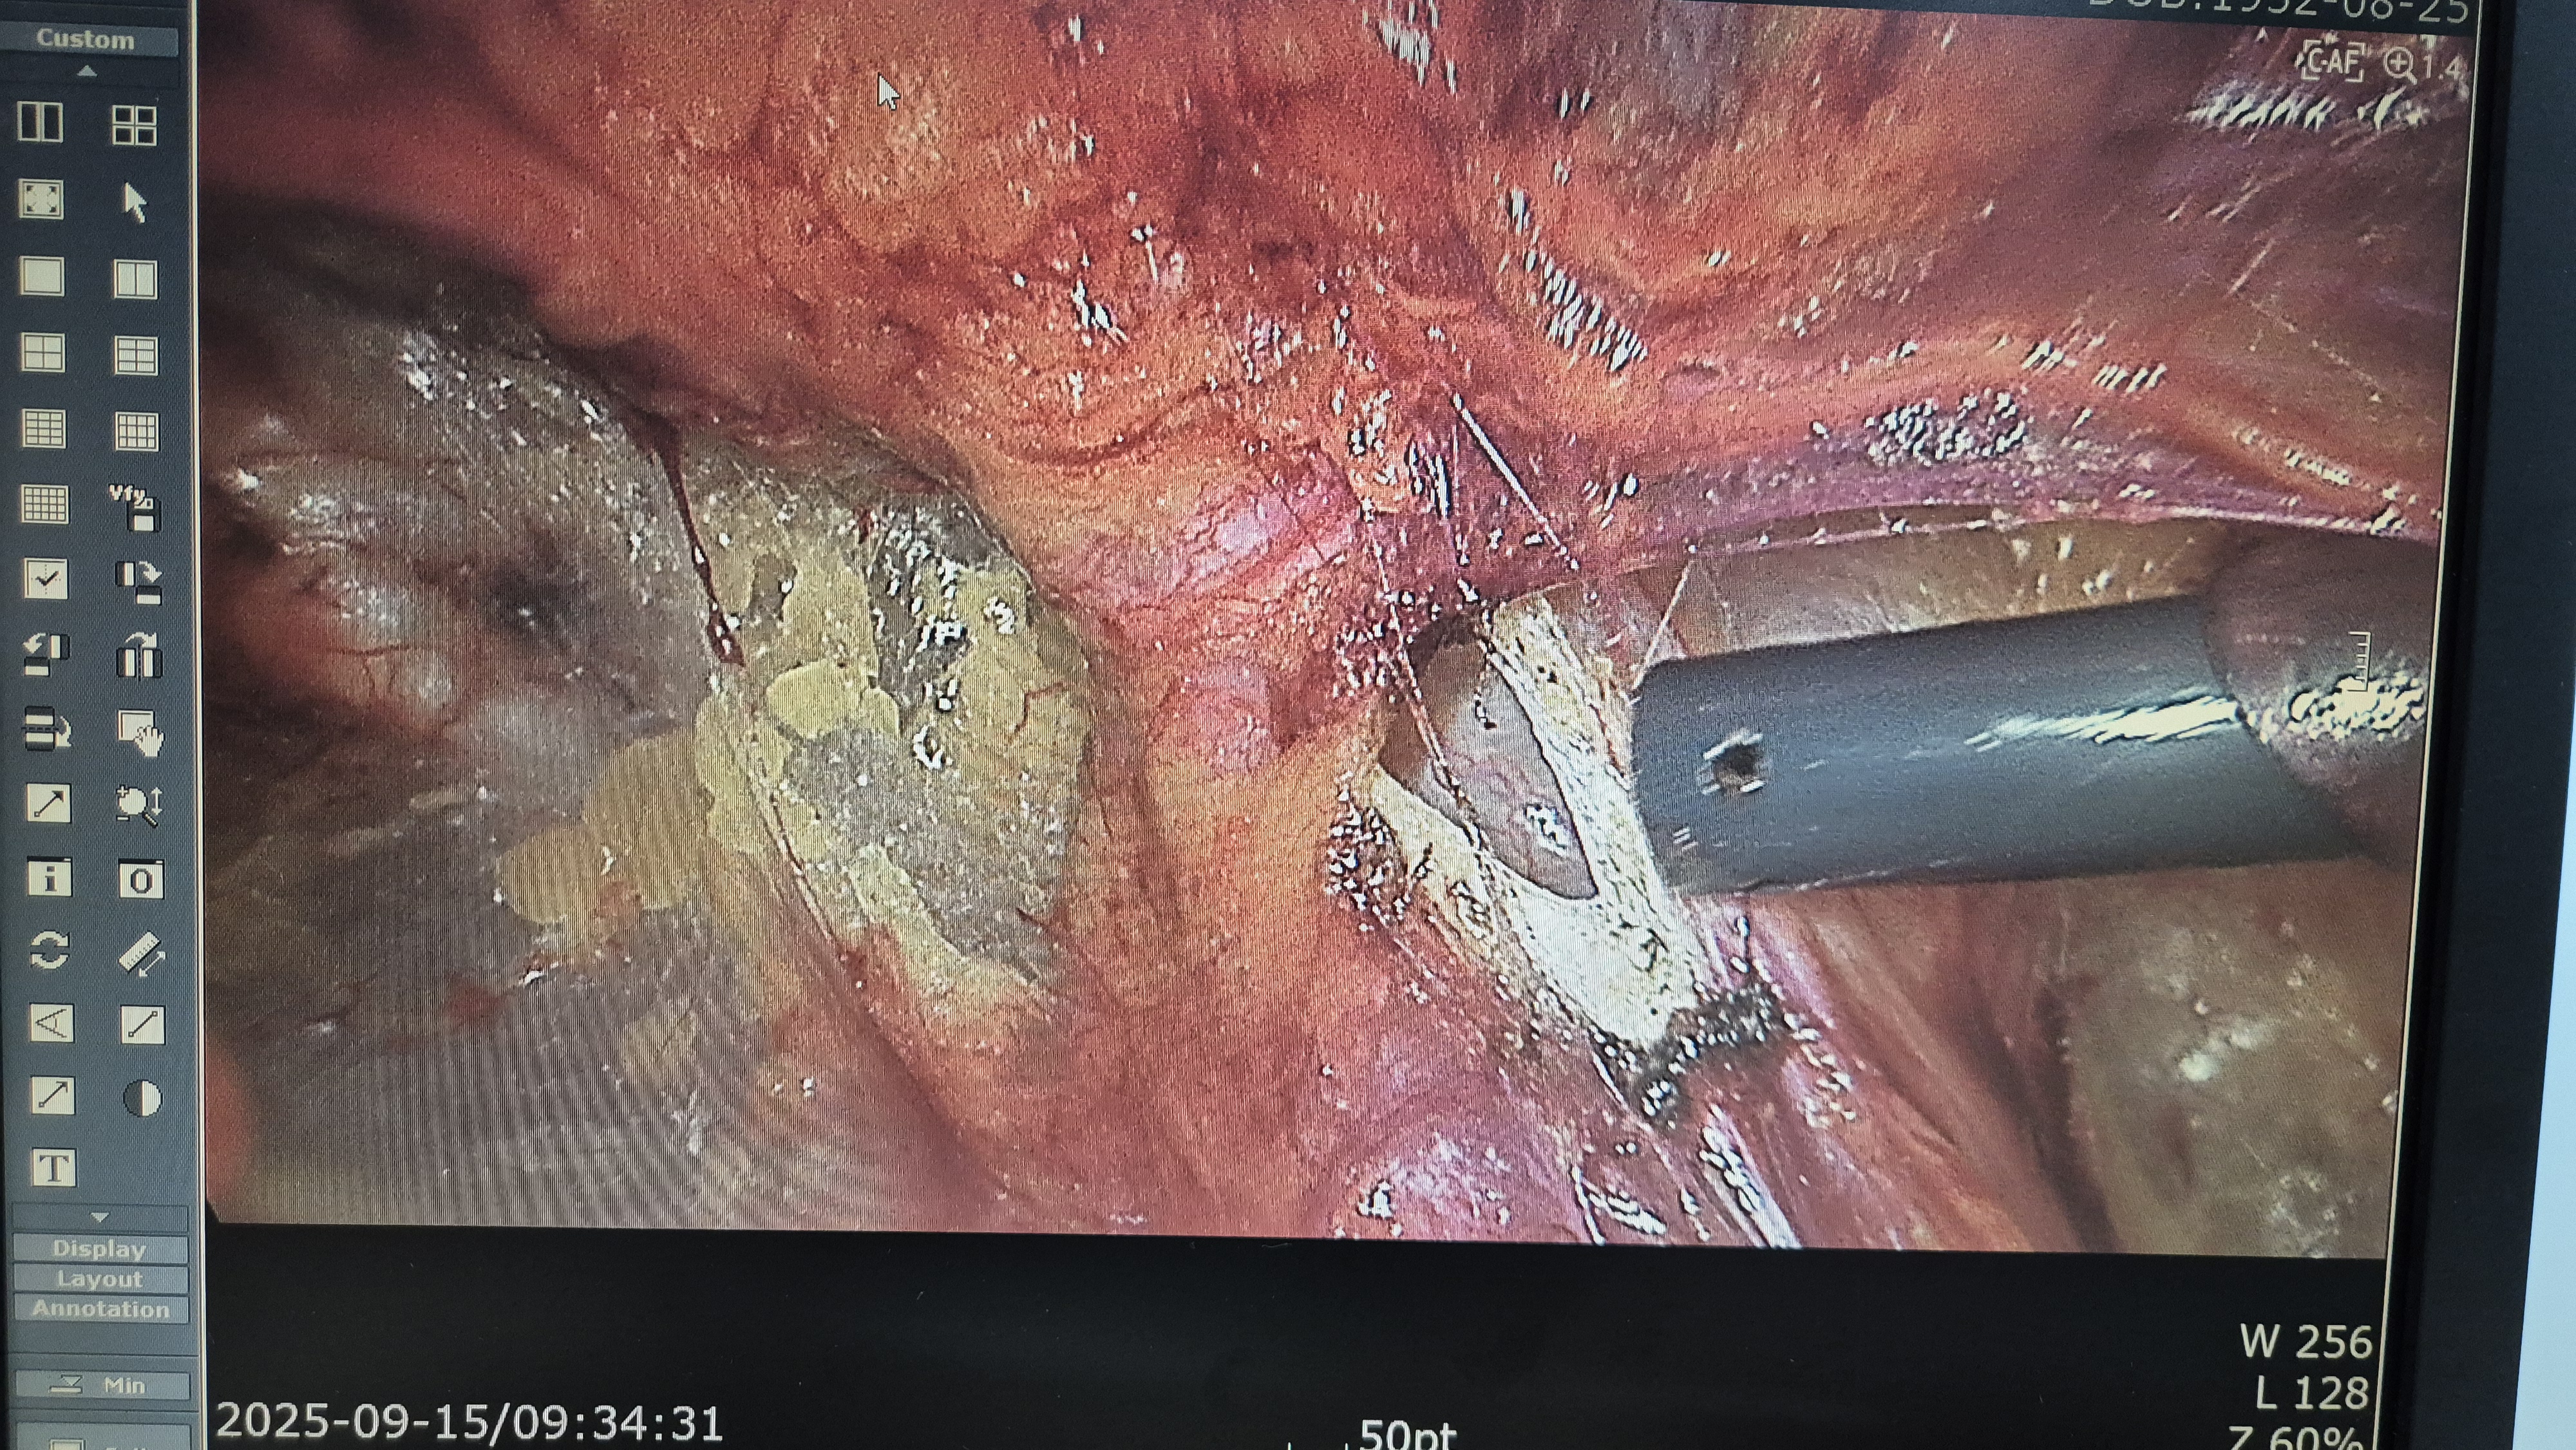

우측 서혜부 종물 주소로 내원하여 초음파 시행후 서혜부 탈장으로 확인되어,

방금 복강경 탈장교정술을 시행했습니다.

탈장 확인후.

박리.

메쉬로 고정.

수술은 20분 걸렸습니다.